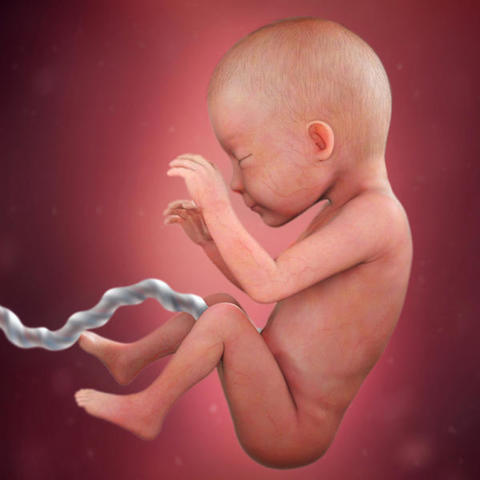

Semana 32

Ahora el bebé engorda a razón de 200 a 300 gramos a la semana, por lo que su aspecto exterior cambia considerablemente.

Su cabeza está proporcionada con respecto al resto del cuerpo, aunque hay que tener en cuenta que los niños tienen la cabeza más voluminosa que los adultos.

Las uñas han completado su desarrollo y si es un chico sus testículos ya se encuentran dentro de la bolsa escrotal.

En cambio sus órganos internos perfeccionan su funcionamiento, pero nada más.